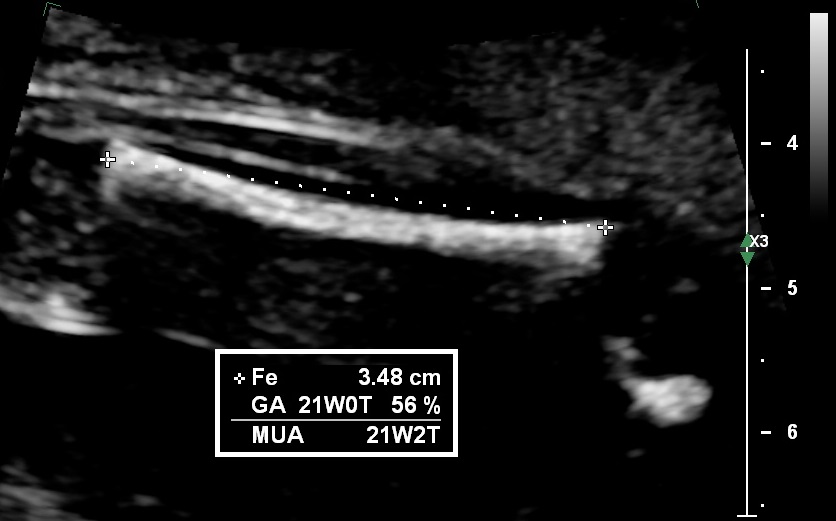

Once the image is satisfactory, the callipers should placed on the outer edges of the femoral bone (outer to outer) excluding the trochanter.